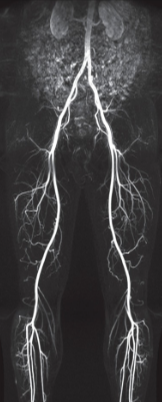

CE MRA (Contrast Enhanced Magnetic Resonance Angiography)?

By using short TR and TE, heavily T1WI are acquired. The surrounding tissues are highly saturated, producing very small signals, while the blood is relatively less saturated by contrast agents, so images of good contrast can be obtained.

It is important to inject the contrast agent through a vein in order to obtain an appropriate contrast of a desired blood vessel, and the time to start obtaining an image after the contrast agent injection plays an important role in separating an appropriate artery image from a vein image.

If the contrast agent shortens the T1 relaxation time, the tumor appears brighter than fat, and CE MRA utilizes the T1 shortening effect of contrast agents.

CE MRA needs a relatively short scan time ,it has higher SNR and CNR than other MRA techniques, and has a wider viewing area, so that the contrast is good, but the resolution is poor.

The degree of carotid artery stenosis, abdominal vessels, and upper and lower extremity arteries are mostly using CE MRA.